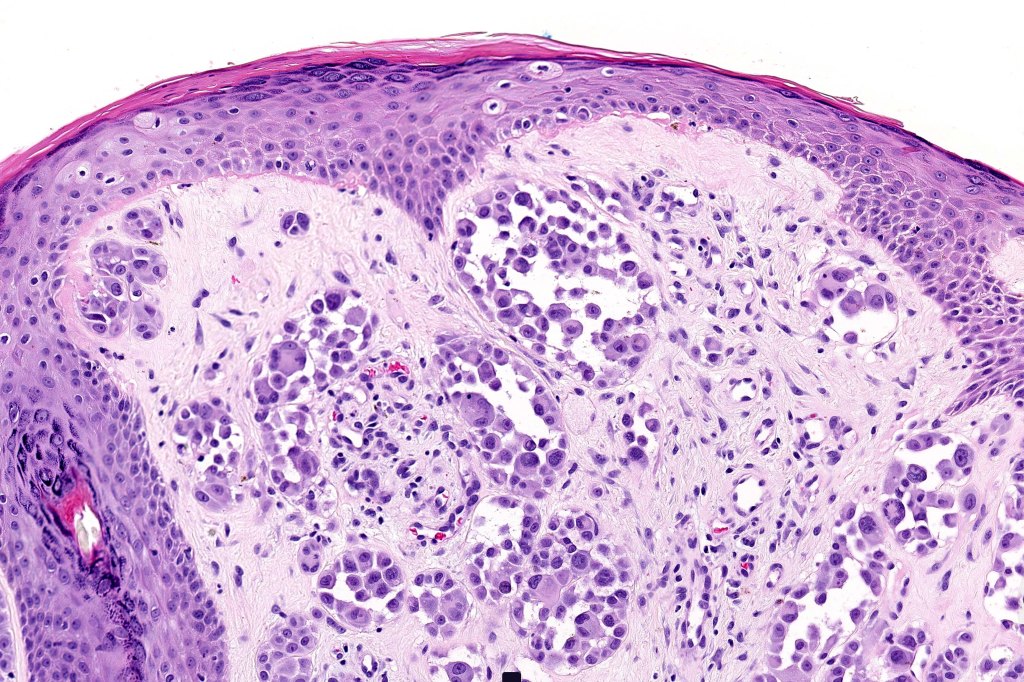

•May show effacement/consumption of epidermis or ulceration

•Peripheral Pagetoid spread

•Large nodules which often show impaired maturation